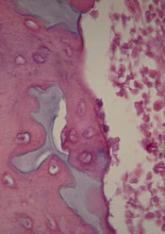

Scientists have found evidence to suggest that a genetic alteration in osteoblasts can induce acute myeloid leukemia (AML). And this provides a...